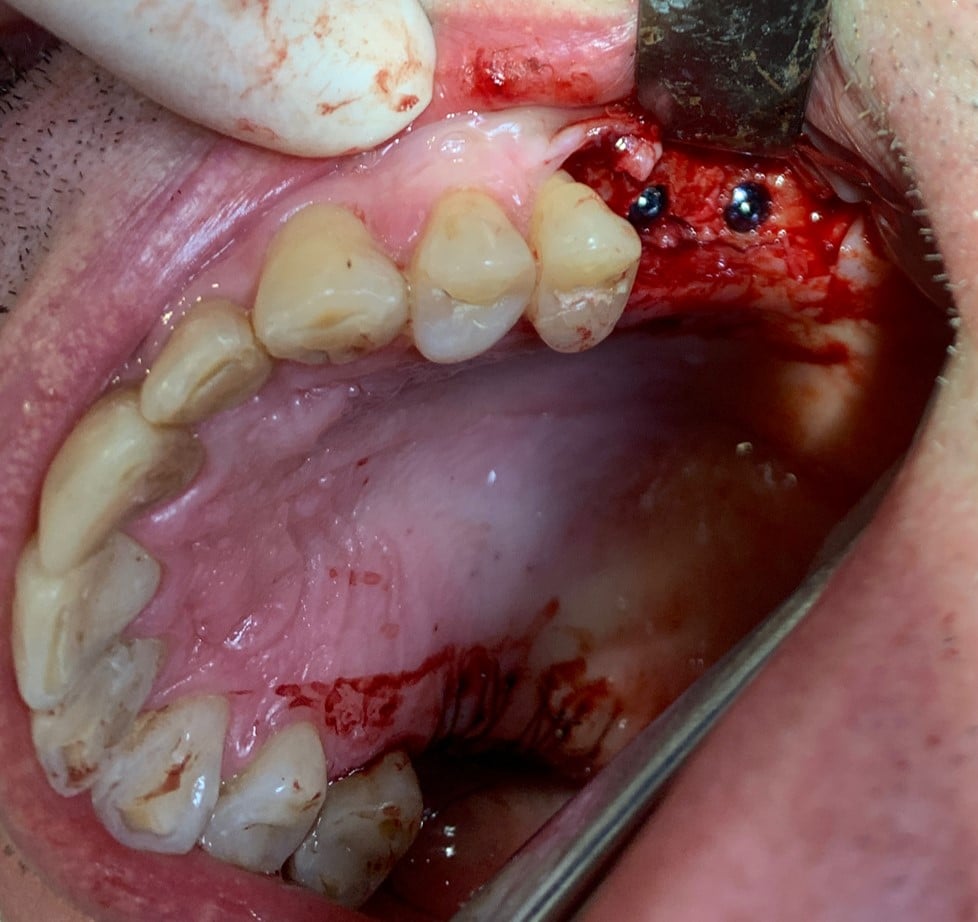

În prima etapă chirurgicală, Dr. Eliza Drăgan a efectuat un lifting de sinus maxilar bilateral.

A doua etapă, inserarea implanturilor, a fost realizată după 6 luni.

Împreună cu pacientul, am optat pentru inserarea implantelor cu ajutorul ghidului chirurgical pentru a plasa implantul în poziția protetică ideală și pentru a permite realizarea coroanelor insurubate pe implant. A fost efectuată scanarea digitală a arcadelor și a ocluziei pacientului, iar împreună cu tehnicianul radiolog de la DigiRay a fost suprapus fișierul .stl al amprentei digitale peste fișierul .dcm de la CBCT, utilizând software-ul 3Shape.

S-a planificat individual poziția și axul de inserție al fiecărui implant.